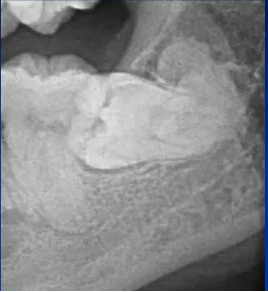

主要诊断:牙体——47龋坏伴根尖炎

牙列——35、45牙缺失,乳牙滞留,38、48智齿埋伏阻生

根尖片进一步诊断

47龋坏伴根尖炎

曲面断层片怎么看口腔精读 | 一次性教你看懂曲面断层片!_https://www.jmylbn.com_新闻资讯_第54张